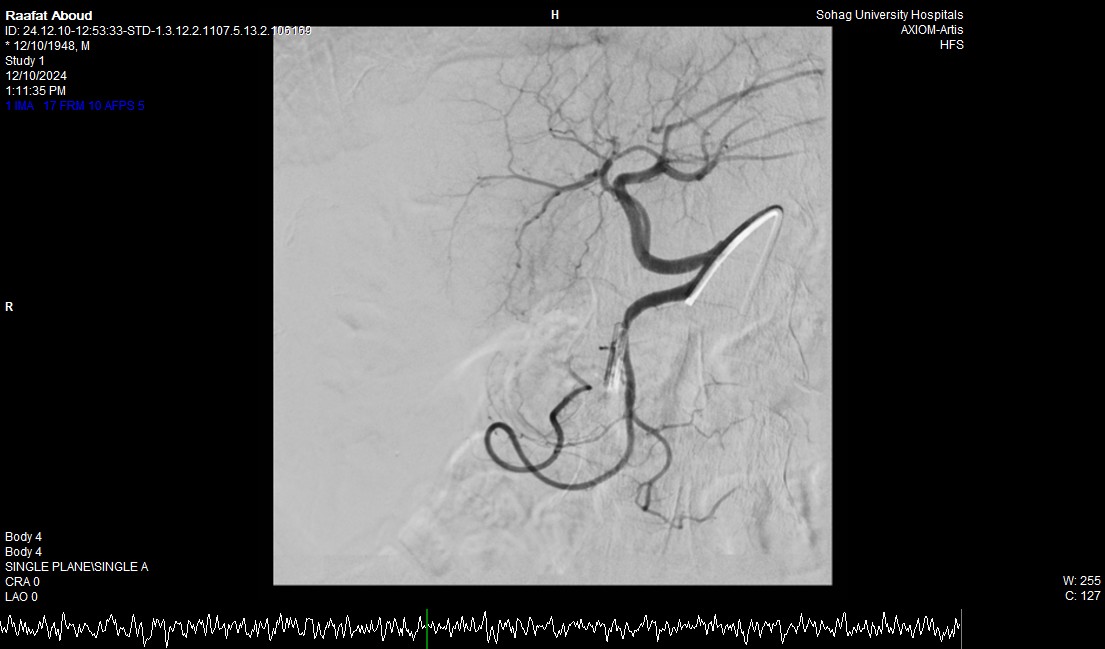

وأضاف الدكتور أحمد كمال المدير التنفيذي للمستشفيات الجامعية جامعة سوهاج، أنه بعد إجراء الفحوصات للمريض تبين وجود قرحة كبيرة بالإثنى عشر وشريان نازف، حيث نجح الفريق في التحكم المبدئي بالنزيف عن طريق تركيب مشبك معدني بالمنظار وحقن للقرحة النازفة، ثم تم استدعاء فريق أطباء وحدة الأشعة التداخلية على الفور وتم عمل غلق للشريان النازف بشكل عاجل من خلال جهاز القسطرة.

وأوضح الدكتور محمد زاكي رئيس قسم الأشعة، أن مثل هذه الحالات تعد من الطوارئ الطبية الخطيرة والتي تستوجب عمل قسطرة شريانية عاجلة لغلق الشرايين النازفه، مشيرًا أن وحدة الأشعة التداخلية تم تزويدها بجهاز أشعة محوري متقدم لاجراء مثل هذه الحالات، وأن هذا النجاح هو نتيجة لتعاون أقسام المستشفى مع وحدة الأشعة التداخلية لتقديم خدمة مميزة للمرضى.